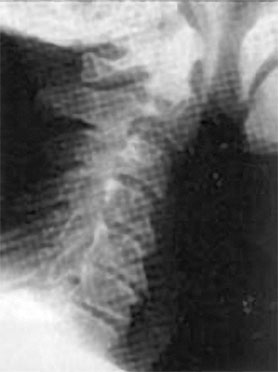

При этом проблемы статики шейного отдела не ограничиваются возрастным гиперлордозом шейного отдела, когда шейные позвонки проваливаются вглубь шеи (рис. 70). Частенько, наоборот, этот изгиб может быть и излишне спрямлен (рис. 71).

Рис. 70. Гиперлордоз шейного отдела

Рис. 71. Спрямление шейного отдела позвоночника